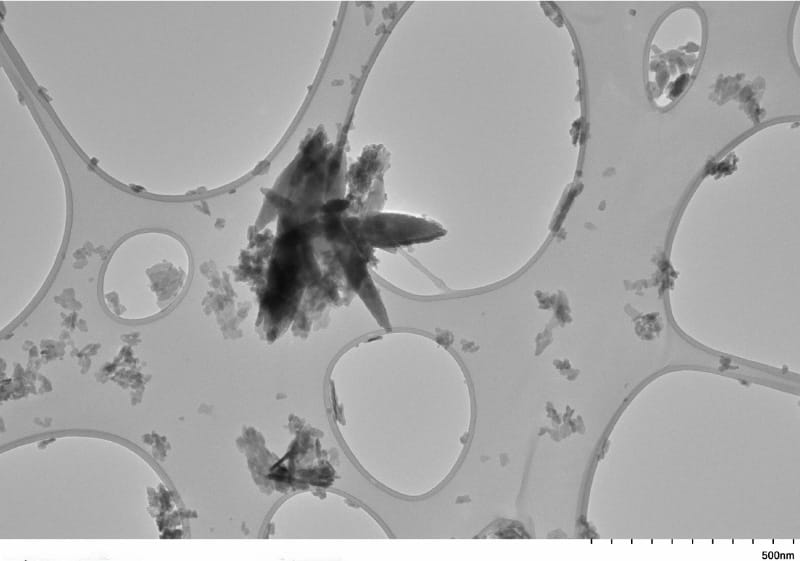

Los microplásticos —fragmentos menores a 5 mm— y los nanoplásticos —de tamaño inferior a los 1000 nanómetros— están presentes en todos los rincones del planeta, desde el suelo y el aire hasta los cuerpos humanos. Su detección en órganos como los pulmones, el hígado, la sangre y la placenta ha sido documentada, pero ahora también se hallan en la acumulación de grasa dentro de las arterias del cuello, y en cantidades inquietantes.

Un estudio reciente presentado en la conferencia Vascular Discovery Scientific Sessions de la American Heart Association reveló que la placa de las arterias carótidas de pacientes con antecedentes de accidente cerebrovascular o síntomas relacionados contenía hasta 2888 microgramos de microplásticos por gramo de tejido, una cifra 51 veces mayor que la encontrada en tejidos arteriales sin obstrucción. Incluso en personas con placa, pero sin síntomas, la concentración fue 16 veces mayor que en las arterias saludables.

Estos hallazgos fueron obtenidos tras analizar las arterias de 48 personas: 35 donantes sin acumulación de placa, seis pacientes con placa pero asintomáticos, y siete pacientes con síntomas claros de obstrucción, como ictus, miniictus o pérdida temporal de visión. Todos ellos se sometieron a cirugía para eliminar la obstrucción, lo que permitió recolectar muestras para su análisis químico y genético.